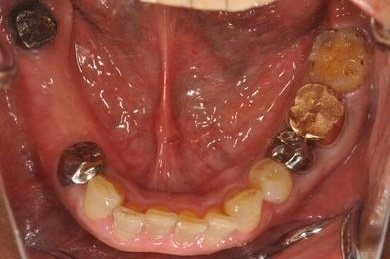

インプラントの症例写真 IMPLANT

インプラント治療+セラミック治療

| 主訴 | 部分入れ歯のバーが舌に当たるため、奥歯2本のインプラント治療を希望。 | ||||||||||||||||||||||||||||||||

| 治療方針 | 右下欠損部分をインプラント治療にて、機能的・審美的回復を行う。 | ||||||||||||||||||||||||||||||||

| 治療内容 | インプラント2本、メタルボンドセラミッククラウン8本、メタルボンドセラミック用土台6本 | ||||||||||||||||||||||||||||||||